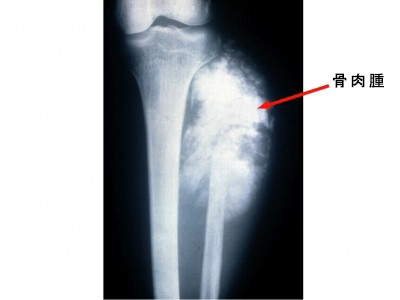

日々の症例 210 骨肉腫 210 30歳代 男性 右下腿の腫脹と疼痛 画像所見 骨胸部単純x線写真と造影ct 冠状断と横断像 右腓骨骨幹端 骨幹に骨硬化と骨膜反応を伴う不整な骨破壊像がみられる 筋の腫脹も目立ち 同部で深部静脈は閉塞していた

骨肉腫

骨肉腫 Wikipedia